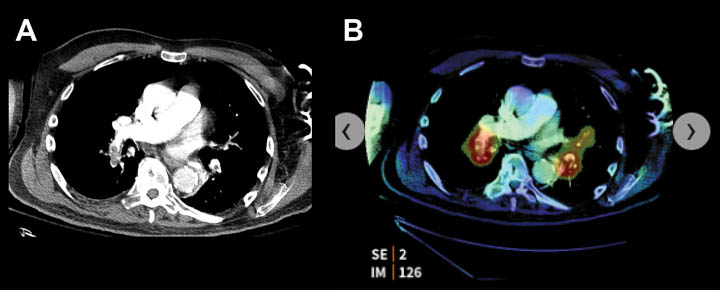

UMass is piloting several FDA approved AI algorithms developed by aidoc, a vendor specializing in diagnostic algorithms that highlight acute abnormalities on CT. This AI based software runs in the background as the radiologist works, flags a case in the reading queue as high priority if an abnormality is detected and produces a color coded overlay to indicate the abnormality.

- Subtle, isointense, left subdural hemorrhage on head CT.

- AI based software highlights the area of hemorrhage, color coded in red.

Data collected at UMass Memorial Healthcare in collaboration with aidoc.